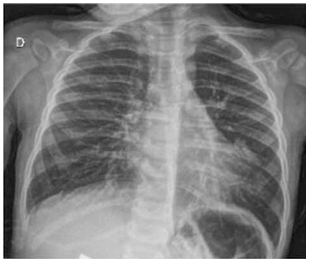

Paciente de 8 anos com asma mal controlada e trazido para avaliação em pronto-atendimento por sintomas de tosse seca e desconforto respiratório há um dia. À admissão, encontra-se em regular estado geral, taquidispneico, com FR = 48 ipm, SatO2 = 86% em ar ambiente; presença de tiragens intercostal e de fúrcula e ausculta pulmonar com sibilos inspiratórios e expiratórios, com tempo expiratório prolongado. Não há prejuízo do nível de consciência. Realizadas três inalações com salbutamol e ipratrópio nas doses adequadas, além de corticoide sistêmico; mantido em máscara não reinalante.

Após todas essas medidas, paciente segue com desconforto respiratório, FR = 44 ipm, SatO2 = 94% em máscara; ausculta pulmonar com o mesmo padrão inicial. Realizada radiografia de tórax a seguir.

(Arquivo pessoal; imagem usada com autorização)

Qual das alternativas a seguir contém a conduta mais adequada a ser realizada no momento?